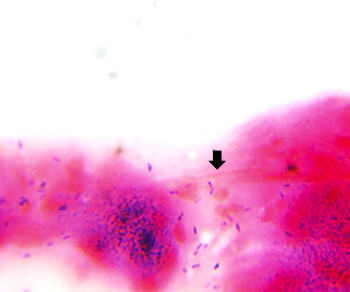

On microscopy Gram

stain showed plenty of inflammatory debris along

with violet colored ovoid spores resembling Microsporidia

(Fig 3.a, 3.b). On Giemsa stain, deep blue oval

spore like structures were seen (Fig 3.c.).

| Fig

3a: Gram-stained smear showing

violet-colored ovoid spores suggestive of

Microsporidia (Gram stain, ×1000

magnification). |

Fig

3b: Gram stained smear showing violet

colored ovoid spores resembling Microsporidia

(Gram stain, ×1000 magnification) |